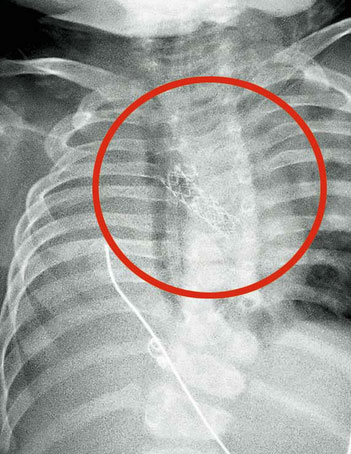

近两天,郑大伯出现胃痛、发热,咳嗽加剧。在家人再三劝说下,他来到杭州市肿瘤医院住院治疗。肺部CT检查显示:考虑右肺中央型肺癌,伴周围阻塞性可能。

检查时发现,大伯的右肺支气管内可见异物堵塞,表面包裹着白色坏死物。经过仔细查找,最终在气管粘膜处发现了一块黑色鱼脊骨。

取出鱼脊骨,医生也吓了一大跳:鱼脊骨直径为1厘米,高为0.6厘米。